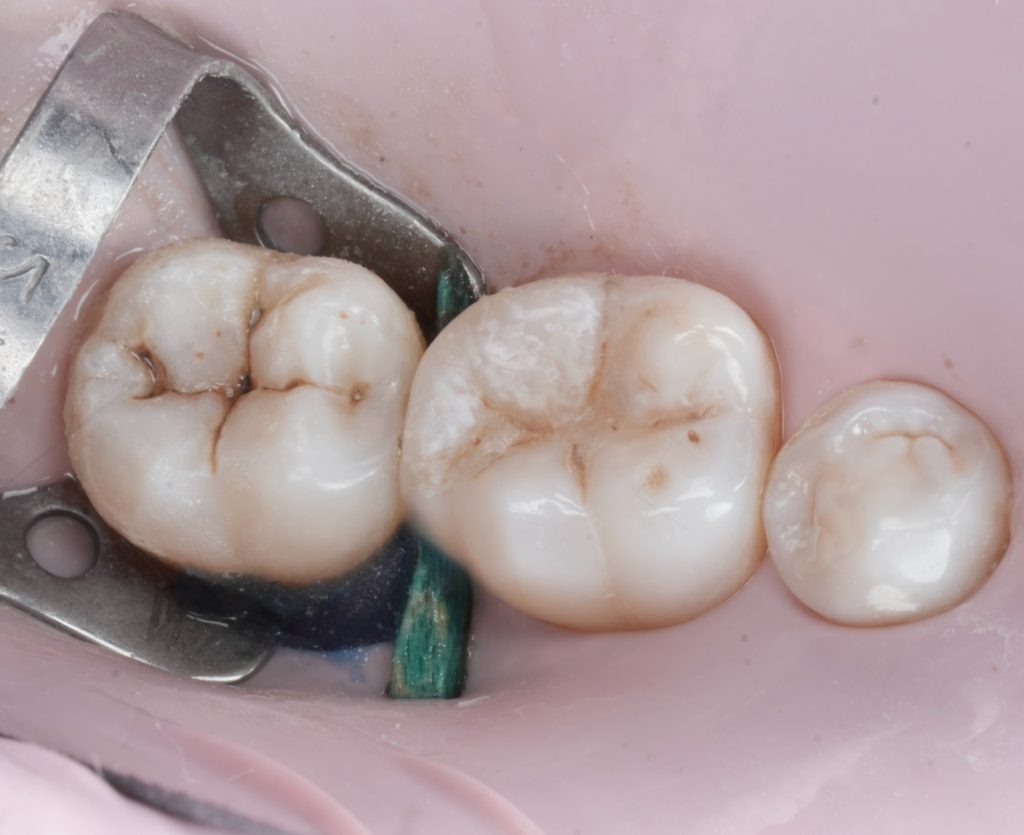

4.5 Composite Build-up

A micro-hybrid sculptable composite was placed in controlled increments:

- Initial dentin shade layer to rebuild internal anatomy

- Proximal wall built using the matrix as a guide

- Occlusal anatomy sculpted cusp-by-cusp

- Final fissure staining for natural texture

- Light cure from multiple angles for optimal polymerization

The restored proximal wall regained proper height, contour, and emergence.

4.6 Finishing & Polishing

The occlusion was verified in maximum intercuspation and excursive movements.

- Tight, healthy proximal contact

- Excellent emergence profile that supports papilla health

- Natural occlusal anatomy

- Smooth margins fully blended with adjacent enamel